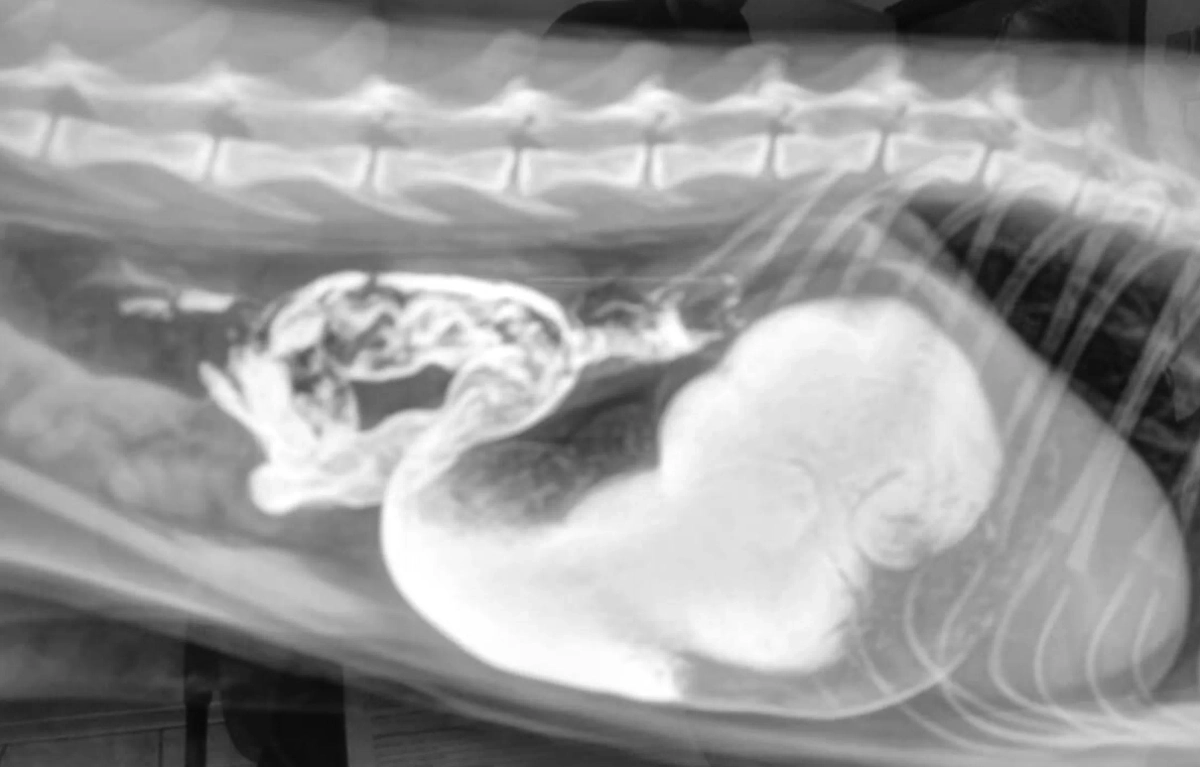

Рентген Ватсона. Фото © Telegram / Моя Ветклиника

Ветеринары Москвы спасли полуторагодовалого мэйн-куна по кличке Ватсон, который попал в клинику в плохом состоянии из-за инородного предмета в желудке — кусочка пробкового коврика. Об этом сообщается в телеграм-канале Московского объединения ветеринарии.

«Хирург Дмитрий Абызов провёл экстренную операцию и извлёк предмет, который озадачил врачей и владельцев. Он напоминал кусок пробки от шампанского: неужели кот «хранил» это в себе с давно прошедших новогодних праздников?» — говорится в сообщении.

После удачной операции Ватсон быстро начал восстанавливаться, а его владельцы вскоре выяснили, что «пробка» на самом деле была частью детского развивающего коврика. Мейн-кун незаметно ото всех грыз его.